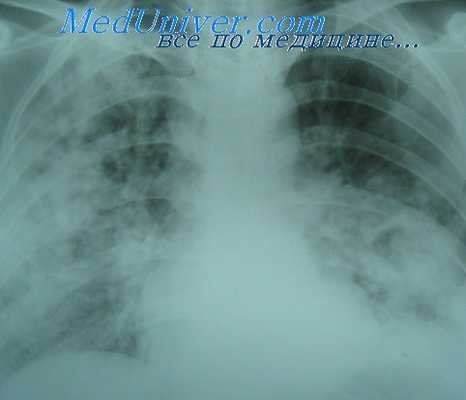

Однако при сочетанных ранениях груди и массивной кровопотере объем травмы и большой объем инфузионной терапии на 3-4-е сутки после ранения может привести к развитию ОРДС. Клинические проявления ОРДС характеризуются резким ухудшением состояния с одышкой, цианозом. В легких прослушиваются влажные рассеянные храпы на фоне жесткого дыхания. На рентгенограммах появляется двусторонняя диффузная инфильтрация легких. Несмотря на ингаляцию кислорода, введение глюкокортикоидов и диуретиков, гипоксия и отек легких нарастают. В таких случаях реаниматологам приходится переходить на продленную ИВЛ в режиме гипервентиляции с минутным объемом от 10 до 14 л, с положительным давлением в конце выхода от 5 до 15 см водн. ст.

Операции в условиях эндотрахеальной анестезии часто сопровождаются нарушениями функции легких. Выраженность этих нарушений может быть ми-нимальной, без явных клинических проявлений или значительной, с осложнен-ным течением послеоперационного периода. Наиболее частым осложнением являются ателектаз и дистелектаз легких, которые могут привести к развитию послеоперационной пневмонии. Ателектаз - образование участка безвоздушной легочной ткани вследствие нарушения про-цессов, поддерживающих воздушность и объем респиронов в этой зоне. Сохра-нение частичной пневматизации патологически измененной зоны легких при по-явлении признаков нарушения оксигенации крови и усиления венозного приме-шивания в легких носит название дистелектаза, рентгенологически описывает-ся как симптом гиповентиляции. Наиболее тяжелым осложнением является острое легочное повреждение (ОЛП) и респираторный дистресс-синдром (РДС).

При выявлении признаков дыхательной недостаточности исключаются возможные причины ее развития – пневмоторакс, эндобронхиальная интубация, наличие нерасправленных во время торакотомических операций участков лег-ких. При отсутствии указанных состояний предполагается наличие у больного синдрома ОПЛ – при снижении респираторного индекса (РаО2/FiO2) менее 300 мм.рт.ст., а при его снижении менее 200 мм.рт.ст. – острый респираторный дистресс-синдром (ОРДС).